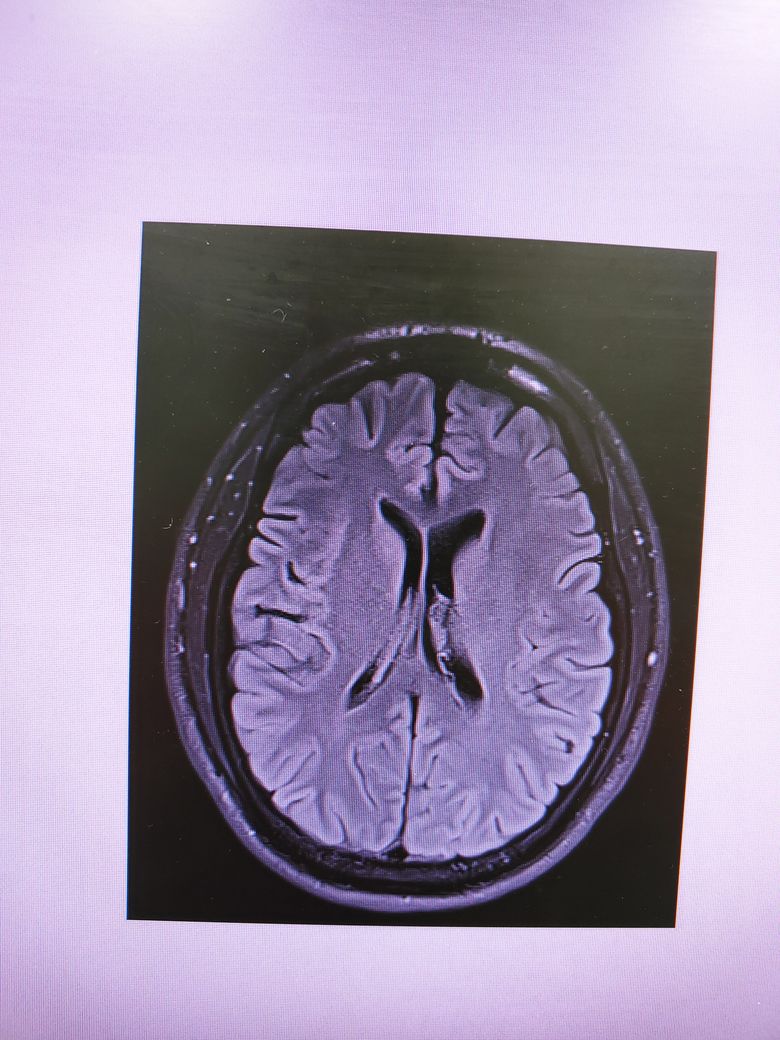

뇌 mri 판독 가능한지요..

요즘 멍한 증상이 지속돼서

일단 mri를 찍어봤네요.

특이사항은 없다는데

한 번 더 볼수있을까해서요.

사진이 정말 많네요..어떤 걸 올려야할 지 모르겠네요.

• 1번 째 사진

4컷만으로는 MRI에 대한 충분한 판독이 어렵지만 큰 이상은 없는것으로 보입니다.

특이 이상소견은 보이지 않으나 mri의 경우 4장으로 판단하는 것이 아닌 각 단면마다의 연속적인 영상을 보아야 알수 있습니다. 그리고 각 setting마다 볼수 있는 것도 다르며 보다 명확한 평가를 위해서 담당 선생님께 보다 구체적인 설명을 들으시길 바라며 최근 멍한 증상이 심해졌다면 뇌파 검사 등이 요구될수 있습니다. 우선적으로 기존에 다니셨던 병원을 내원해 진료를 보시고 추가적으로 신경과 내원 또한 고려해볼 수 있습니다. 감사합니다.

올려주신 사진 상에서는 이상소견이 확인되지 않습니다.

MRI의 경우 이렇게 몇컷만 보는것이 아니고 전체를 확인해야하기 때문에 다른 신경과 전문의 진료를 받아보시고 MRI 판독을 요청해보시는게 좋겠습니다.